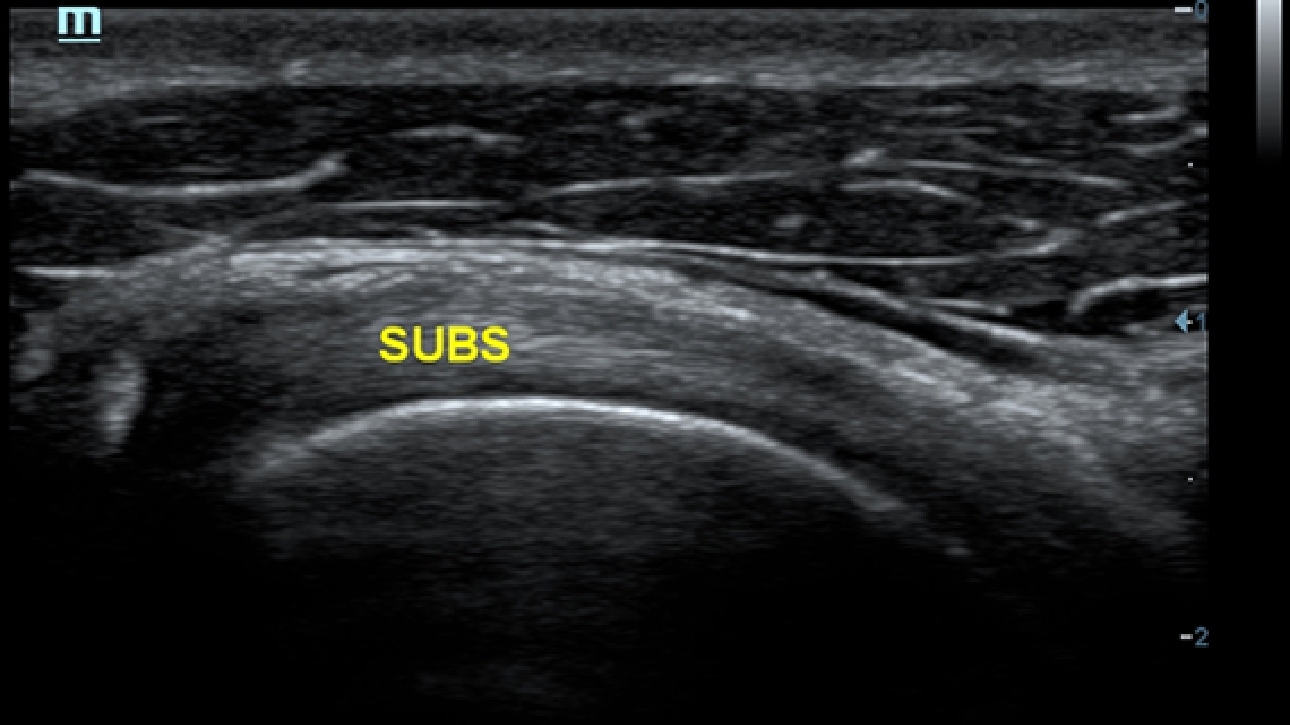

X-Insight es la soluci├│n intuitiva para una mejor visualizaci├│n.

La nueva soluci├│n de Mindray es una excelente transformaci├│n desde la continua comprensi├│n de las necesidades cl├Łnicas del usuario, combinada con la evoluci├│n de la tecnolog├Ła de los ultrasonidos m├Īs puntera. Repleto de vitalidad, con el ├║nico objetivo de visualizar el futuro y evitar los l├Łmites, el ec├│grafo DC-60Exp con X-Insight est├Ī constantemente mejorando con una escalabilidad aumentada. Como un socio personal, el equipo de ultrasonidos DC-60 Exp con X-Insight se centra en lo que verdaderamente importa, ayudando al usuario a administrar su pr├Īctica cl├Łnica con facilidad y seguridad.

Bas├Īndose en una profunda comprensi├│n de las necesidades del usuario, el sistema de ultrasonidos DC-60 Exp con X-Insight est├Ī dise?ado para ofrecer una alta eficiencia con im├Īgenes de precisi├│n, la cual se ve potenciada por una claridad inmediata, una inteligencia excepcional y benefici├Īndose de una c├│moda experiencia.